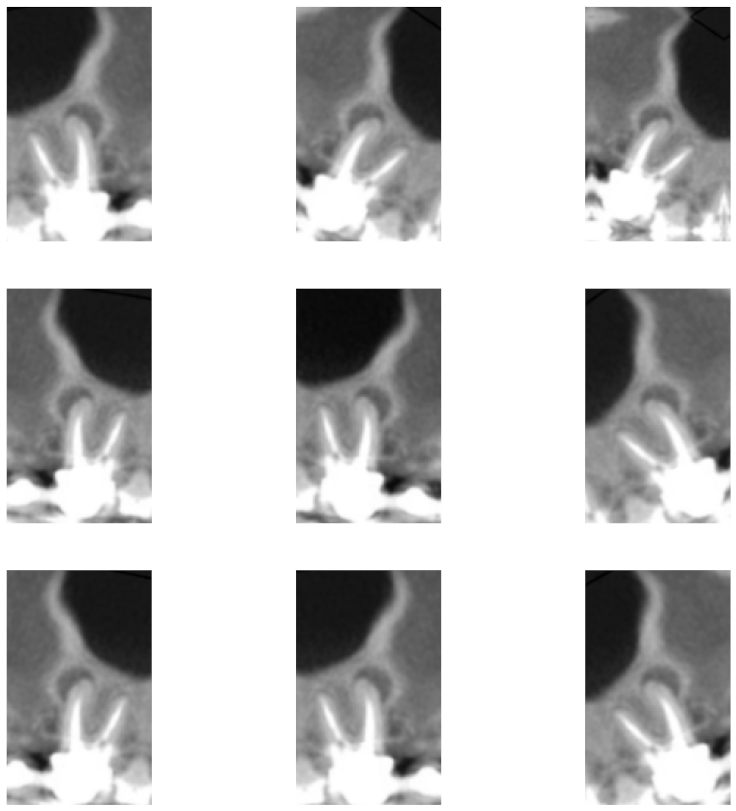

4.1. Database

| Classification | Number of Samples | Features |

|---|---|---|

| Healthy | 454 | Teeth without lesion |

| Small Lesion | 276 | Teeth with lesion of 0.5 to 1.9 mm |

| Large Lesion | 270 | Teeth with lesion of 2.0 mm or greater |